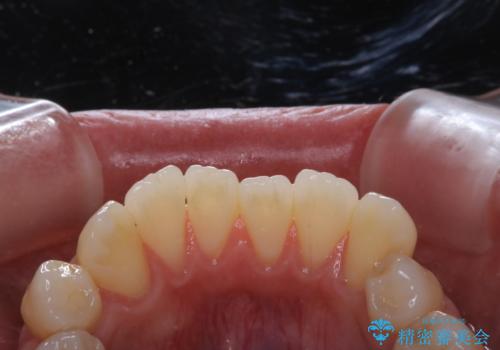

- 歯周病が心配で予防をしていきたいとのことでした。PMTC60分コースを行いました。

歯周病とは、細菌による感染症です。歯周病菌を取り除くには、歯周ポケットの中を機械的に掃除することです。

歯周病の原因は、歯にべったりと付着するプラーク(細菌の塊)や歯石です。そこから歯周病菌が引き起こす炎症により、歯を支える歯周組織が破壊され、最終的には歯が抜け落ちてしまうという怖い病気です。

もっとも、効果的な治療法がPMTC(歯科医院で専門的な機械や材料を使用してクリーニング)を定期的に行うことです。